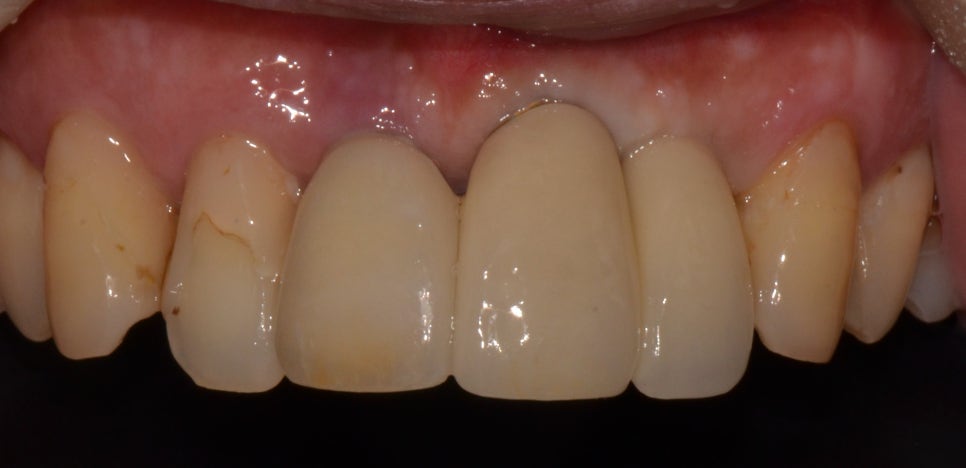

치료 후

2023년 9월 4일 (6개월 소요)

좌측 상악 전치와 측절치 발치를 한 후 염증이 심한 케이스이기 때문에 발치를 하고 난 후에 3개월 정도는 염증 치료를 진행하였습니다. 그리고 임플란트를 식립해 주었는데요. 염증으로 인해 잇몸뼈의 상태가 좋지 않아 잇몸뼈 이식도 진행하였습니다. 발치를 하고 나서는 임시 틀니를 사용할 수 있도록 해드렸으며 염증이 우선적으로 개선되어야 했기 때문에 구강관리에 대한 설명을 드리고 현재는 많이 개선된 상태입니다.

임플란트 시술에서 잇몸뼈를 중요하게 봐야 하는 이유는 뼈의 양이 부족하거나 상태가 좋지 않다면 지지를 해 줄 수 있는 부분이 없어 고정이 잘되지 않기 때문이었는데요. 고정이 잘되지 않으면 식립을 하더라도 흔들림이 있을 수 있고 음식을 먹을 때마다 흔들림이 있다면 제대로 저작력 또한 잘되지 않았습니다. 그래서 잇몸뼈의 상태가 좋아야 임플란트 치료가 가능하다는 점도 같이 참고해 주시길 바랍니다.